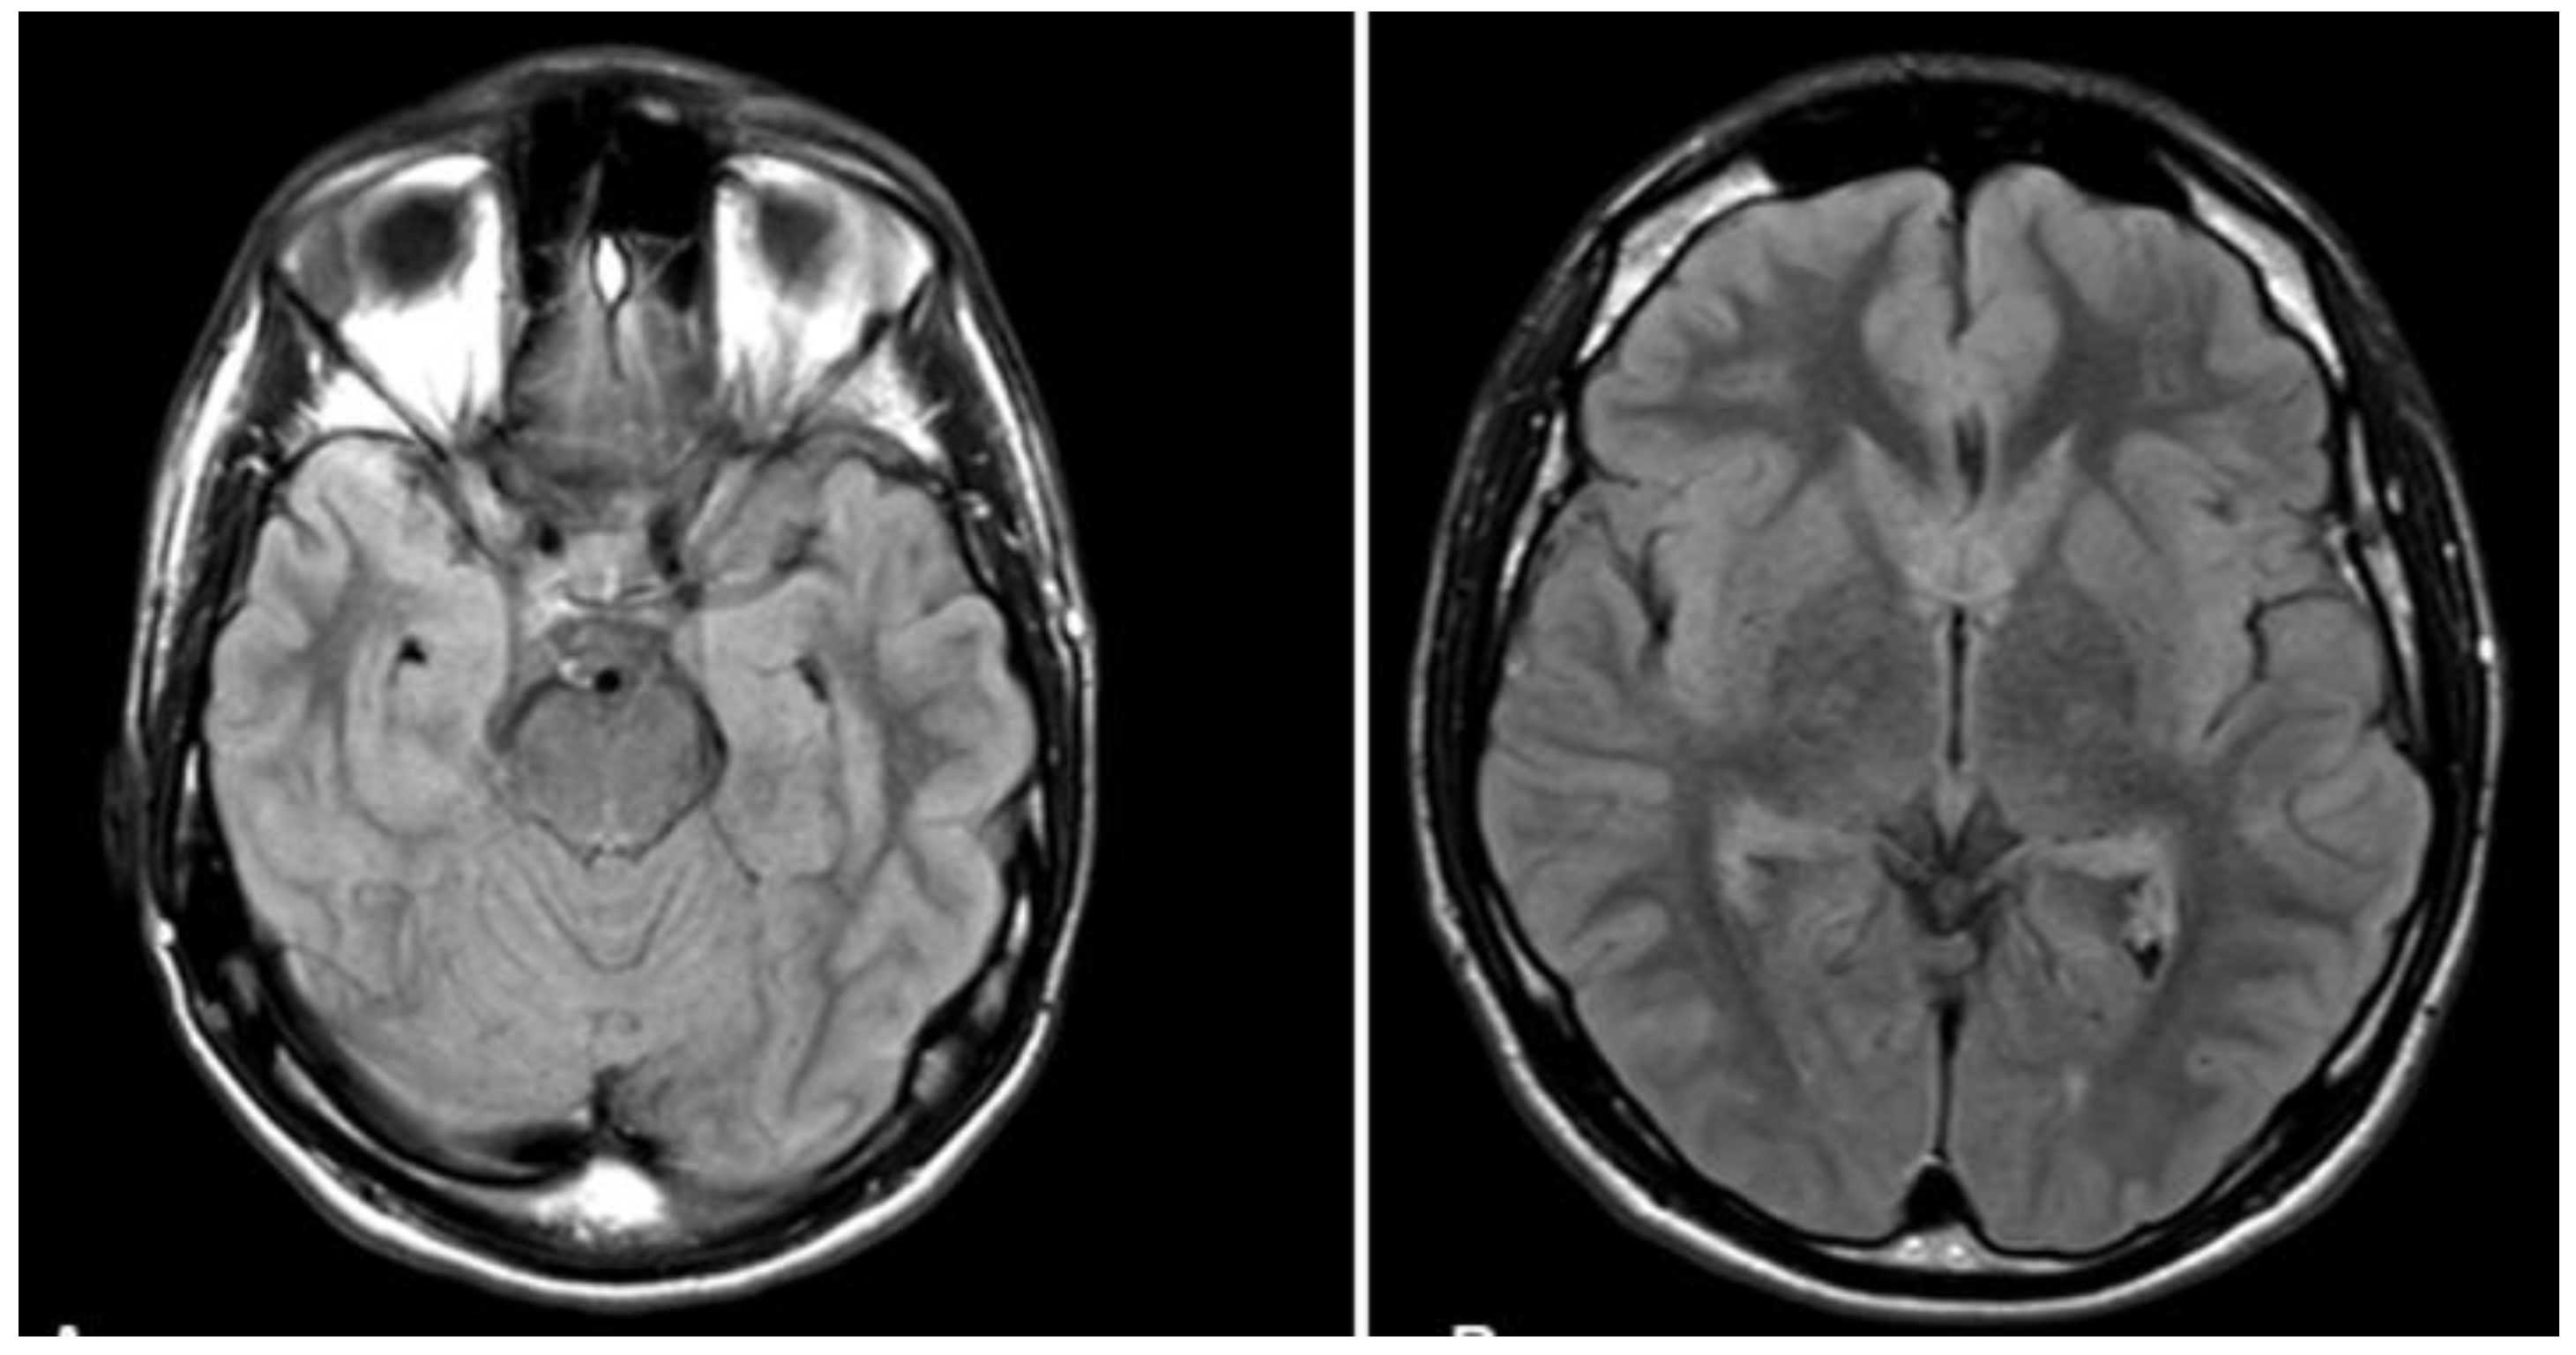

2.6. Analysis of Pupil Size

We processed the data using Pupil Player software. During data processing, we eliminated blinks and data exceeding typical ranges. In other words, we eliminated data indicating pupil size beyond the interval of 2–4 mm, referring to the typical pupil diameter in bright light, this to exclude 12% of the data. We then calculated the average pupil size (in mm) during each condition, namely, the average pupil size during retrograde retrieval, anterograde retrieval, construction of next week events, construction of next month events, and construction of the next year events. Figure 2 illustrates pupil size in each condition. Because data involved many measures (i.e., each condition involved pupil size measured across hundreds of frames), we were able to conduct statistical analysis for pupil size, as depicted below. This was unlike the specificity score that involved single data for each condition.

Pupil sizes for each condition are shown in Table 1. Mean pupil size was larger during future (M = 2.52, SD = 0.41) than during past thinking (M = 3.16, SD = 0.75), t(198) = 7.05, p < 0.001, Cohen’s d = 1.06. Analysis also demonstrated larger pupil size during anterograde than during retrograde past thinking, t(198) = 12.23, p < 0.001, Cohen’s d = 1.71. No significant differences were observed across the three future thinking conditions, F(2, 297) = 1.25, p = 0.29, η2 = 0.031.

Figure 2. Illustration of L’s pupil diameter during past and future thinking.